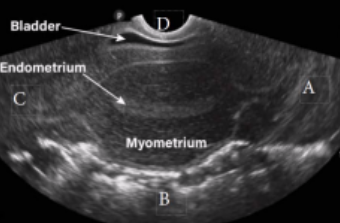

What type of fibroid is depicted in this image?

a. Intramural

b. Submucosal

c. Subserosal

d. Pedunculated

Subserosal

Where is this fibroid located in the uterus?

a. Anterior

b. Posterior

c. Cervical

d. Fundal

Anterior